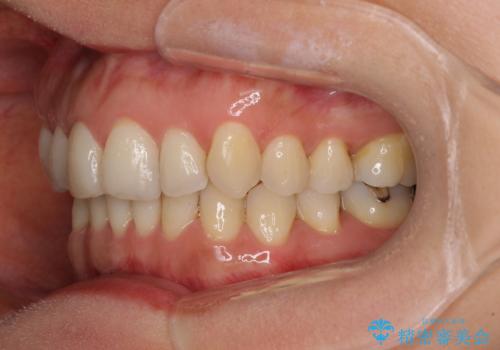

矯正治療の後戻り インビザライン・ライトによる矯正治療

- 患者様

- 40代女性

- 矯正装置

- インビザライン・ライト

- 治療期間

- 11ヶ月

- 矯正治療の後戻りを気にして来院された患者様です。

後戻りは軽微であったので、インビザライン・ライトにより矯正治療を行うこととしました。